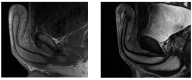

Methods: A systematic review of the literature from 1956 to 2022 was conducted in accordance with the general guidelines recommended by the Primary Reporting Items for Systematic Reviews and Meta-analyses (PRISMA) statement. We included full papers published from 1956 to 2022. We also described a case report of a 23 year old Bulgarian male affected by penile paraffinoma who underwent a 2-stages surgical technique.

Results: A total of 152 cases have been reported, with a median age of 37.9 ranging from 18 to 64 years. Six different techniques have been described in the whole literature: bilateral scrotal flap, simple excision of the paraffinoma with primary closure, two-stage scrotum skin flap, medial prepuce-soprapubic advancement flap technique and penile reconstruction using split thickness skin graft (STSG) or full thickness skin graft (FTSG). An analysis of the distribution among early and late complications was then carried out.

Conclusion: In our experience, among the variety of surgical techniques described, a two-stage penile reconstruction using scrotal skin results in excellent cosmetic and functional outcomes, with a low rate of complications.